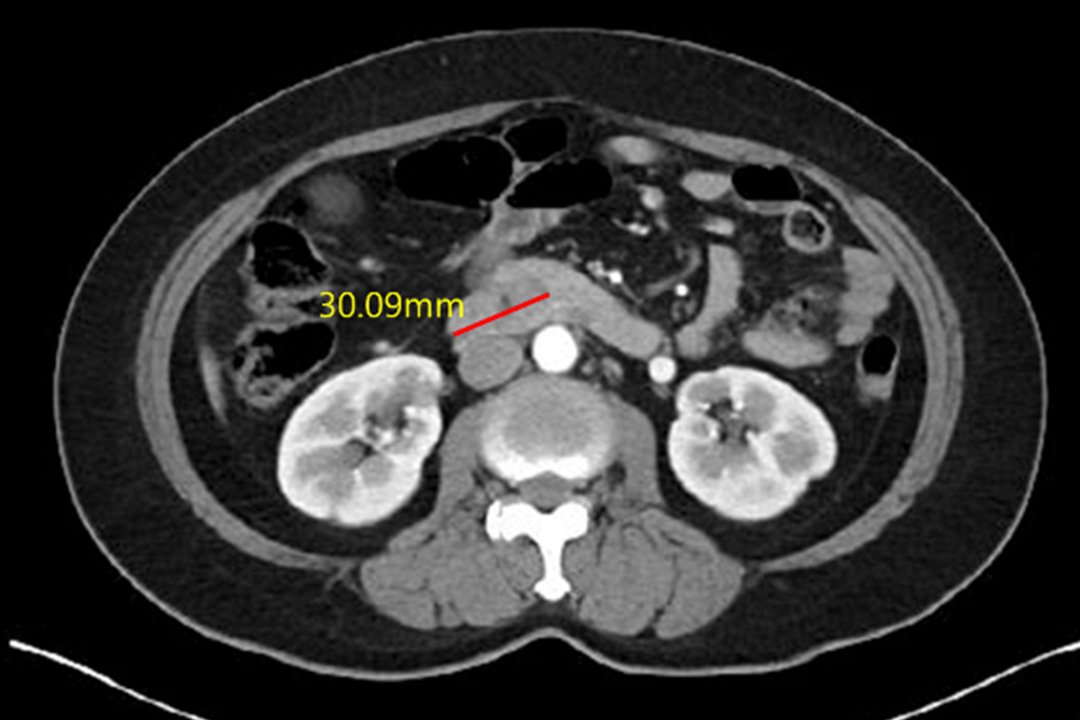

Case of treatment

아미랑에서 치료하신 분들의 소중한 치료사례를 담았습니다.